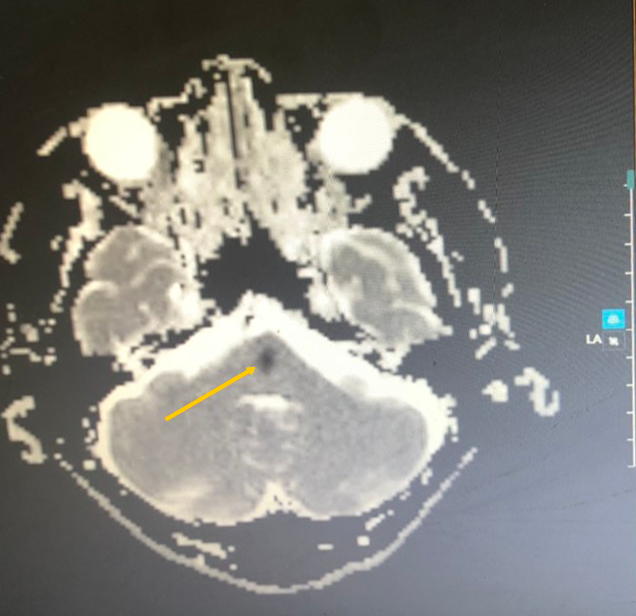

Bệnh viện lập tức phát y lệnh khẩn “Code Stroke”, ưu tiên nhân lực, máy móc cứu người đột quỵ. Trung tâm Chẩn đoán Hình ảnh và Điện quang can thiệp nhanh chóng chụp cộng hưởng từ (MRI). 10 phút sau, kết quả cho thấy bệnh nhân bị nhồi máu cầu não, không tắc mạch máu lớn nội sọ.

“Tổn thương nằm ở vùng thân não trọng yếu, nơi tập trung các bó sợi thần kinh đi xuống tủy sống, có hệ thống lưới đảm nhiệm chức năng thức - tỉnh. Bệnh nhân có triệu chứng đột quỵ khoảng 4-4,5 giờ. Dù còn giờ ‘vàng’, ê-kíp không thể chậm trễ, càng lâu biến chứng càng nặng nên phải tiết kiệm từng giây phút”, bác sĩ Minh Đức cho biết.

Vị trí nhồi máu não vùng thân não (trái) và sau khi được can thiệp tiêu sợi huyết gây đột quỵ qua hình ảnh MRI (phải). |